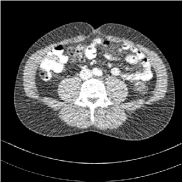

Refer to caption FBPRMSE = 194.09 HURefer to caption FBPRMSE = 194.09 HURefer to caption PWLS-ULTRARMSE = 43.40 HURefer to caption PWLS-ULTRARMSE = 43.40 HU

Refer to caption FBPConvNetRMSE = 34.24 HURefer to caption FBPConvNetRMSE = 34.24 HURefer to caption SUPER-FCN-DataTermRMSE = 31.21 HURefer to caption SUPER-FCN-DataTermRMSE = 31.21 HU

Refer to caption SUPER-FCN-ULTRARMSE = 28.82 HURefer to caption SUPER-FCN-ULTRARMSE = 28.82 HURefer to caption ReferenceRefer to caption Reference

Figure 5: Reconstructed images of slice 150 of patient L192 using of FBP, PWLS-ULTRA, FBPConvNet, SUPER-FCN-DataTerm, and SUPER-FCN-ULTRA, respectively, shown along with the reference.

Fig. 5 shows reconstructions using FBPConvNet, SUPER-FCN-DataTerm (i.e., β=μ=0𝛽𝜇0\beta=\mu=0), PWLS-ULTRA, and SUPER-FCN-ULTRA, respectively. For SUPER-FCN-DataTerm, when optimizing the data-fidelity term, we start with the deep network’s output and ran 5 iterations for the data-fidelity term to avoid overfitting to the analytical FBP images. In Fig. 5, obviously, FBPConvNet significantly suppresses noise and artifacts compared to PWLS-ULTRA, but it also over-smooths many details (e.g., features in the zoom-in box) in the reconstruction. SUPER-FCN-DataTerm, by enforcing data consistency, helps reduce overfitting issues and reconstructs image details and tissue boundaries better compared to the standalone FBPConvNet. Our SUPER-FCN-ULTRA method, however, exploits richer prior information (via the union of learned sparsifying transforms) and explicit network regularizer and outperforms the SUPER-FCN-DataTerm approach. Additional such comparisons for other selected test slices are included in the supplement (Fig. 15).